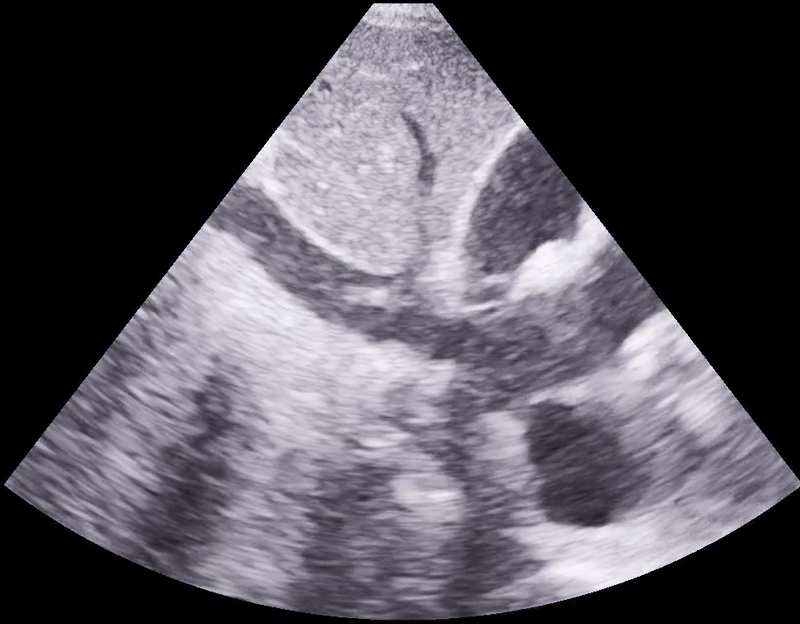

Diastolic right ventricular collapse.

POCUS cardiac: You won’t diagnose cardiac tamponade unless you look, so that’s the biggest take home point, please just get up and look. Once you’re on your feet with ultrasound probe in hand, a plethoric IVC is the most sensitive finding, and diastolic right ventricular collapse is the most specific finding. In the above clips, you are visualizing obstructive shock. When the heart relaxes and tries to fill during diastole, it cannot because of the pressure applied on the right ventricular free wall by the pericardial effusion.